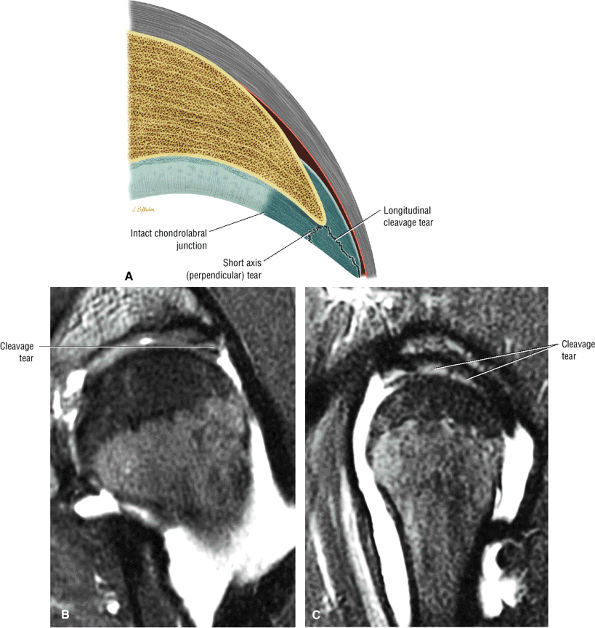

The subgluteus medius bursa is deep to the gluteus medius tendon and the subgluteus minimus bursa is deep to the gluteus minimus tendon.

-

Adductor tendon pathology includes tendinosis, partial tears, and full-thickness tears.

The anterior facet-gluteus minimus attachment (Fig. 3.147): the gluteus minimus is visualized anteriorly on sagittal images through the greater trochanter.

The lateral facet-gluteus medius muscle attachment (see Fig. 3.146)

The superoposterior facet-gluteus medius tendon attachment (Fig. 3.148): the gluteus medius tendon attachment is posterior to the minimus attachment anteriorly and the muscular fibers of the medius attachment as viewed on sagittal images through the greater trochanter.

The posterior facet has no tendon attachments and is covered by the trochanteric bursa (see below).

![]() |

|

FIGURE 3.146 ● (A) Greater trochanter facet anatomy. AF, anterior facet; LF, lateral facet; SPF, superoposterior facet; PF, posterior facet. (B) Osseous attachment sites of the gluteus medius and gluteus minimus tendons to the greater trochanter facets. GMin, gluteus minimus tendon attachment to the anterior facet; GMed, gluteus medius lateral tendon attachment to the lateral facet and main tendon attachment to the superoposterior facet. (C) Sagittal T1-weighted image showing gluteus minimus and medius attachments to the greater trochanter. The minimus tendon attaches to the anterior facet and the medius tendon attaches to the superoposterior facet.

FIGURE 3.147 ● T1-weighted MR arthrograms showing the attachment of the gluteus minimus tendon to the anterior facet in the axial (A) and coronal (B) planes.

The trochanteric bursa (Fig. 3.150) is also referred to as the subgluteus maximus bursa. The largest of the three bursal structures, it covers the posterior facet and partially covers the lateral facet. It is found deep to the gluteus maximus and iliotibial tract and can be visualized anterior to the gluteus maximus on sagittal or axial MR images. It parallels the linear contour (see Fig. 3.150) of the posterior facet. Sometimes two trochanteric bursae are present, a superficial bursa deep to the fascia lata and a deep bursa located medial to the superficial bursa.

The subgluteus medius bursa (Fig. 3.151) is located deep to the lateral aspect of the gluteus medius muscles and tendons. It covers the superior aspect of the lateral facet but is difficult to visualize unless distended with fluid. The superior border of this bursa is at the tip of the greater trochanter.

The subgluteus minimus bursa (Fig. 3.152) is deep to the gluteus minimus tendon and medial and superior to its insertion. It can be seen extending anterior and medial to the minimus tendon on sagittal images through the greater trochanter.